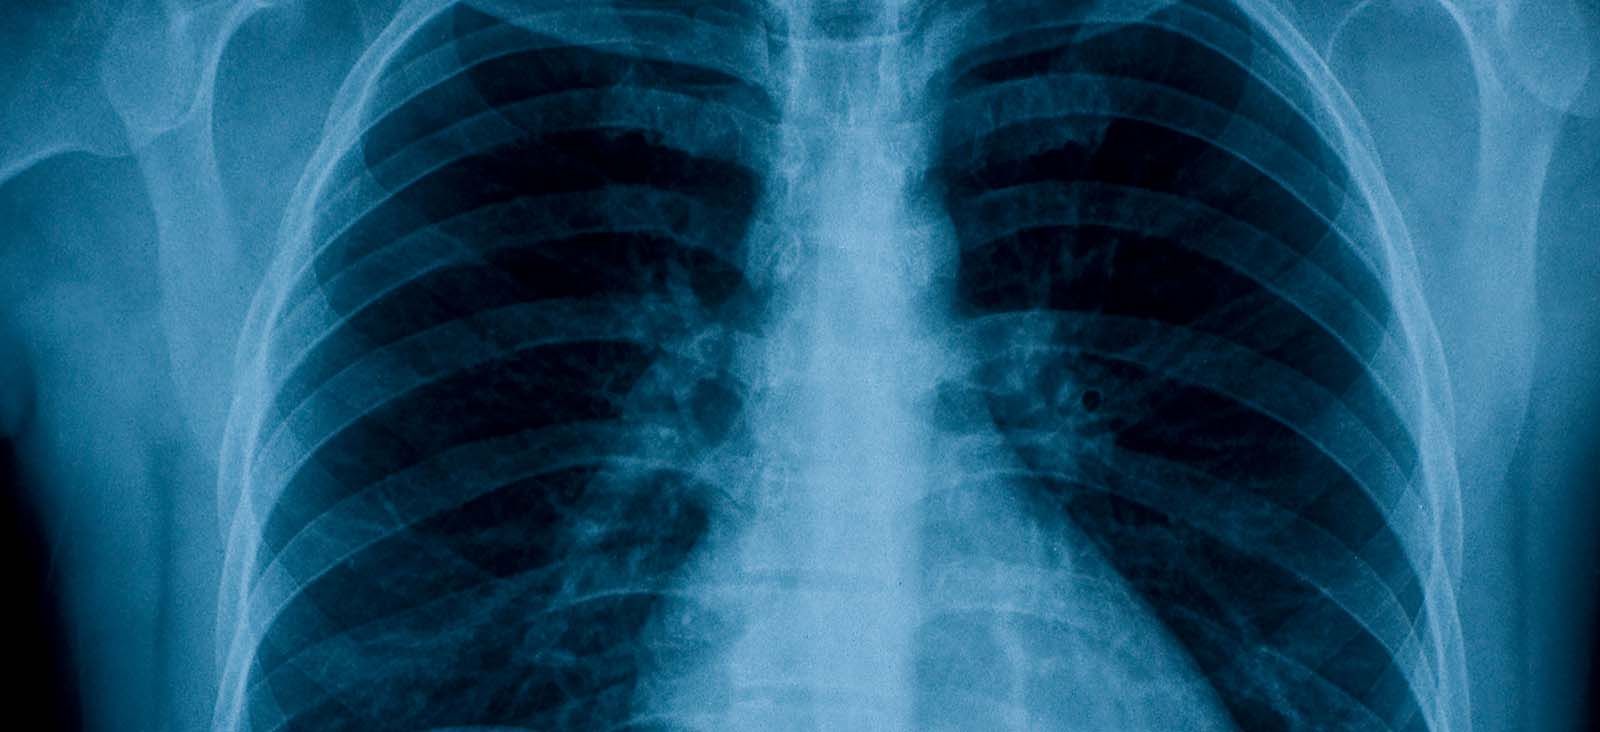

Lungs

University Hospital Outpatient Imaging Services - CT Lung Screening

at Outpatient Building 1801 Inwood Road, 1st FloorDallas, Texas 75390 214-645-9729 Directions to University Hospital Outpatient Imaging Services - CT Lung Screening at Outpatient Building, Dallas Parking Info for University Hospital Outpatient Imaging Services - CT Lung Screening